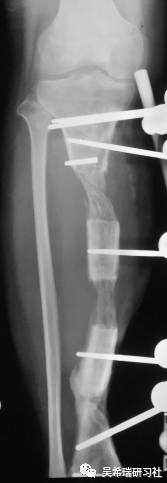

病例7

小腿骨折继发感染骨髓炎反复皮瓣9个月未下地骨质疏松继发肥胖

TIPS:9个月反复皮瓣未下地骨质严重疏松病灶清除后应用表面羟基磷灰石涂层骨圆钉半开放植骨 + 骨搬移骨水泥设计为自行吐出伤口开放换药走路骨质改善、骨愈合治疗足下垂